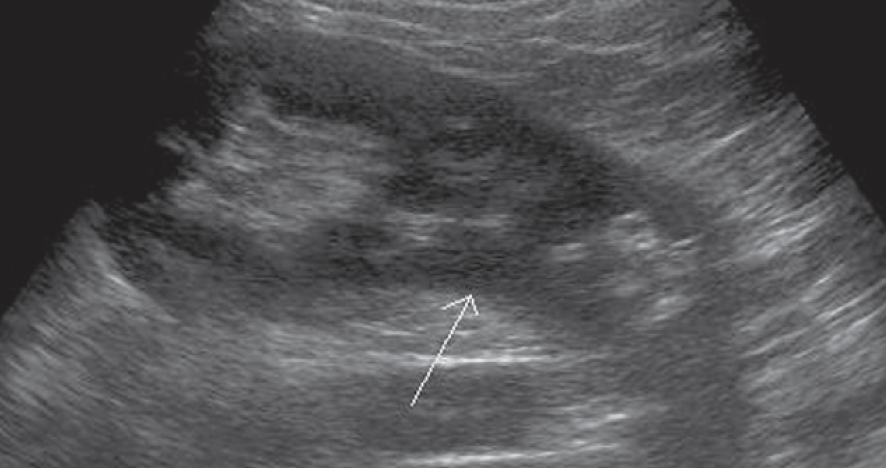

1-Hypertrophied column of Bertin

أعتقد بأن هذا من أهم المتغيرات التي قد يشتبه في كونها ورم. هي ببساطة تضخم لنسيج الكلية parenchyma إلى الداخل sinuses مرورا بين الأهرامات الكلوية medullary pyramids.

يميزه تناسق echogenicity بينه وبين باقي parenchyma بالإضافة لعدم وجود ارتفاع أو تغير ملحوظ في قراءات colour Doppler. غالبا لا يزيد عرضه عن ٣ سم.